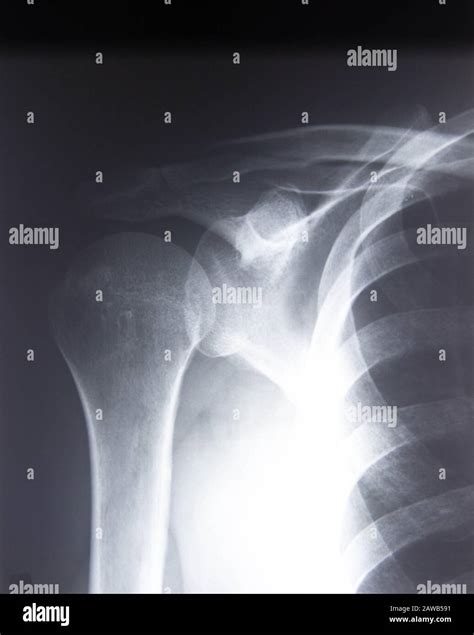

Understanding the importance of an Ac Joint X Ray is crucial for anyone dealing with shoulder pain or injuries. The acromioclavicular (AC) joint is a small but significant joint located where the collarbone (clavicle) meets the shoulder blade (scapula). Injuries to this joint are common, especially among athletes and individuals involved in contact sports or activities that involve falling on an outstretched arm. This blog post will delve into the details of Ac Joint X Ray, its significance, the procedure involved, and what to expect from the results.

An Ac Joint X Ray is a diagnostic imaging technique used to visualize the acromioclavicular joint. This type of X-ray provides detailed images of the bones and the surrounding structures, helping healthcare professionals to diagnose injuries, fractures, or other abnormalities in the AC joint. The procedure is non-invasive and relatively quick, making it a preferred method for initial assessments of shoulder pain.